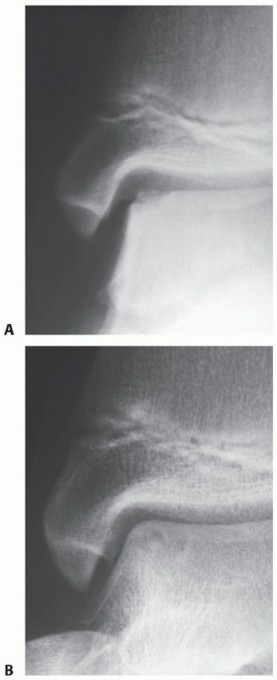

Stage III: articular cartilage breached, high signal changes behind fragment indicating synovial fluid between fragment and underlying subchondral bone (FIG 1)

FIG 1 • A. Arthroscopic view of a full-thickness osteochondral defect at the talar dome. B. Corresponding MRI.*

FIG 2 • A. OCD in a child with open physis. B. Six months later, the lesion is healed with conservative treatment.*